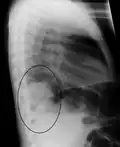

Right upper lobe pneumonia as marked by the circle. -

The discovery of x-rays made it possible to determine the anatomic type of pneumonia without direct examination of the lungs at autopsy and led to the development of a radiological classification. Early investigators distinguished between typical lobar pneumonia and atypical (e.g. Chlamydophila) or viral pneumonia using the location, distribution, and appearance of the opacities they saw on chest x-rays. Certain x-ray findings can be used to help predict the course of illness, although it is not possible to clearly determine the microbiologic cause of a pneumonia with x-rays alone.